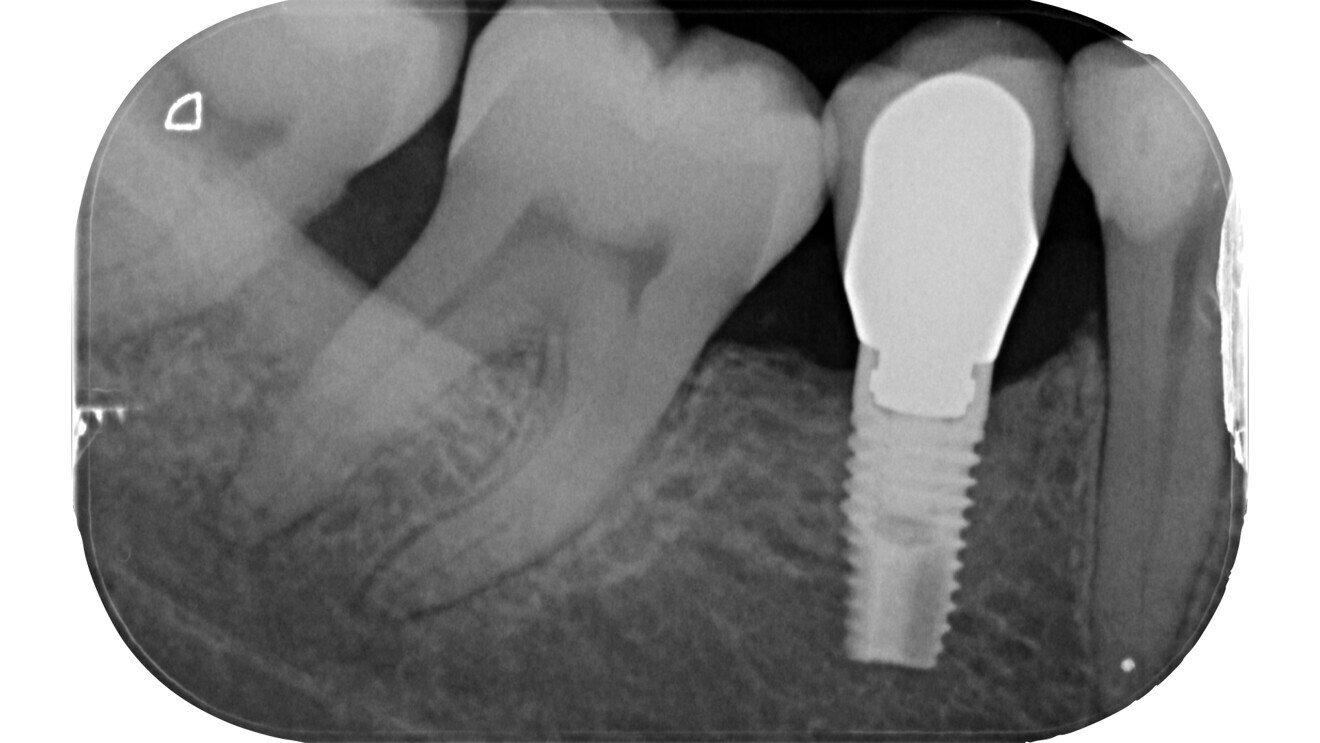

Fig. 20: Post-op radiograph.

A careful analysis of this clinical and radiographic data is of primary importance to achieve a periodontal and restorative diagnosis that could impact on the retention of the tooth. Moreover, it may significantly reduce the risk of gross errors in access cavity preparation. Before focusing on the preparation of the access cavity, the removal of carious tissue and improper restorations gives the opportunity of directly detecting sound dental structure (restorative diagnosis) and avoids contamination of the root canal system during treatment as well.6 The resulting restorative diagnosis covers the identification of cracks, fractures and secondary caries, as well as evaluation of the residual tooth substance—all factors that can influence the prognosis of the tooth.